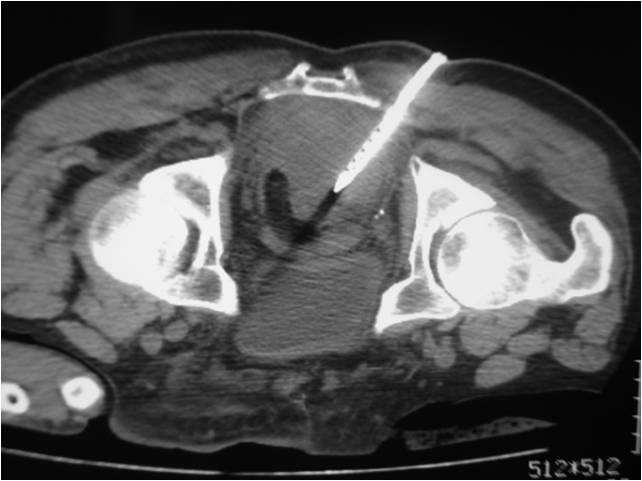

- Placement of a nephrostomy and sump caheter through the greater sciatic foramen into a deep pelvic abscess.

- Paracentisis of a deep pelvic abscess

- Successful catheter placement in a deep pelvic abscess